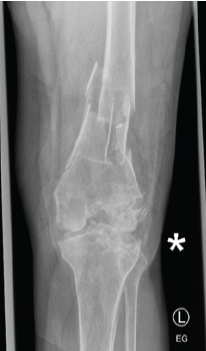

Single-Stage Correction of Genu Recurvatum with Dual-Pillar Plating – A Case Report

V S V Kumar , Velmurugan Srinivasan , S N Muthu Adaikkappan , S Rajasekar , A S Hemapriya

………………………………p.36-43